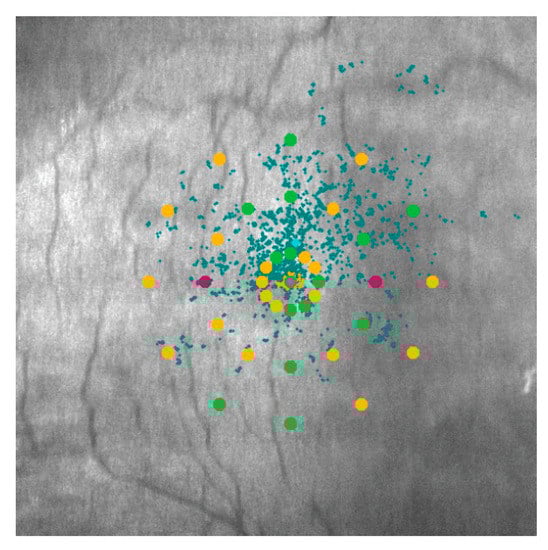

| Fixation P1 (%) | 45.03 (24.89) | 58.21 (26.66) | 88.52 (12.19) | <0.00001 |

| Fixation P2 (%) | 70.2 (20.61) | 81.03 (15.60) | 96.09 (3.66) | <0.00001 |

| BCEA95 (degrees) (median, range) | 46.3 (12.5–187.7) | 34.4 (1.2–155.1) | 4.55 (0.3–23.5) | <0.00001 |